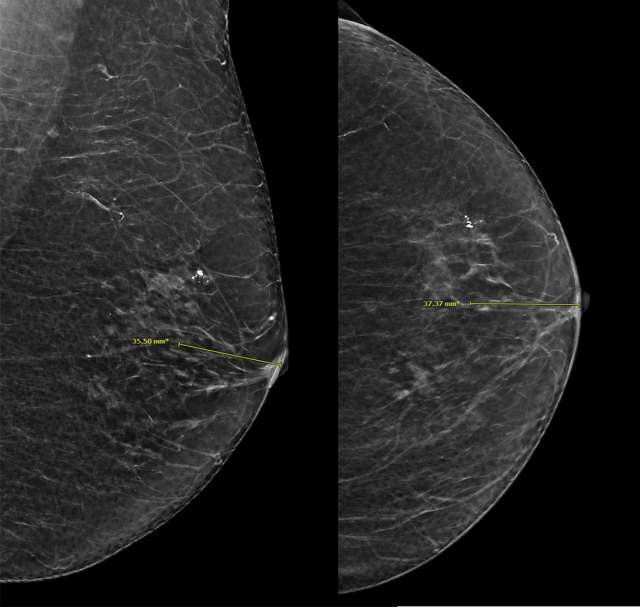

Distance from the nipple measures the distance from the lesion to the nipple to further localize the lesion on different mammographic views (Figure 8).